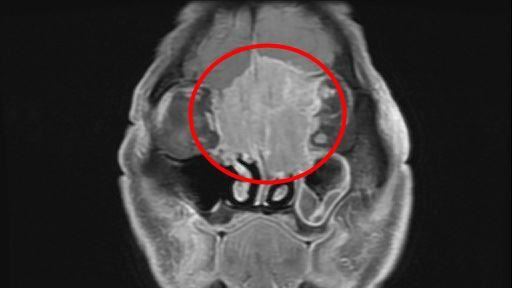

▲黃先生罹患罕見的「嗅神經母細胞癌」,且腫瘤已長到6公分,佔據整個前顱底並侵蝕到鼻樑骨。(圖/慈醫提供)

花蓮慈醫耳鼻喉科副主任周昱甫表示,第一次看到黃先生時,便發現他眉間額頭微凸、眼距較寬,經過電腦斷層掃描、病理切片檢查,確診腫瘤為罕見的嗅神經母細胞癌,且腫瘤已長到6公分,從大腦額葉到雙側眼框到鼻腔上部,佔據整個前顱底並侵蝕到鼻樑骨,雖病人視力未受到影響,但因橫向生長的腫瘤因壓迫到眼外肌,導致病人眼睛無法聚焦,與典型的嗅神經母細胞癌的常見症狀鼻塞、流鼻血等表現症狀大不同。